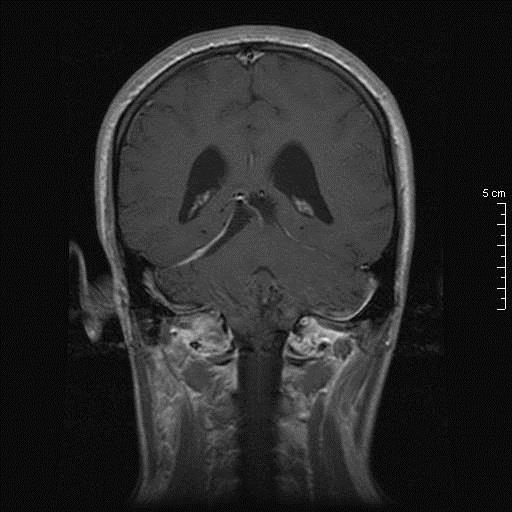

Γυναίκα 34 ετών παρουσιάστηκε με κεφαλαλγία, περιστασιακά διπλωπία και στην εξέταση οίδημα οπτικών θηλών. Η μαγνητική τομογραφία κατέδειξε βλάβη διαμέτρου 26.7 χιλ στην περιοχή της επίφυσης χωρίς ενίσχυση, με πίεση επί του τετραδύμου και σημαντική διάταση του κοιλιακού συστήματος. Σε θέση park bench υποβλήθηκε σε δεξιά πλάγια περιορισμένη ινιακή κρανιοτομία και μέσω της υποσκηνίδιας υπερπαρεγκεφαλιδικής οδού σε ενδοσκοπικά υποβοηθούμενη μακροσκοπικά πλήρη αφαίρεση της βλάβης.

Προεγχειρητικός απεικονιστικός έλεγχος